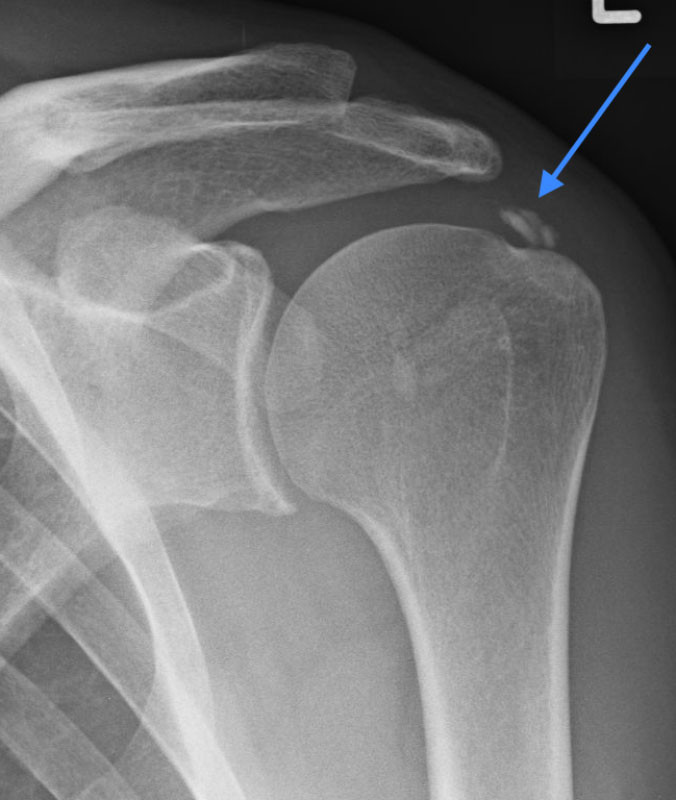

Kalkschulter Tendinosis Calcarea

Das Röntgen-Bild zeigt ein Kalkdepot in der Rotatorenmanschette der Schulter (Pfeil)